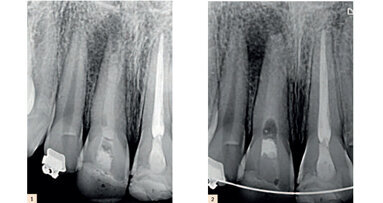

Une patiente se présente avec une douleur intense persistante sur une 16 restaurée avec un amalgame ancien et infiltré. Après examen clinique et radiologique, le diagnostic de pulpite aiguë nous conduit à dévitaliser la dent et procéder à une reconstitution corono-radiculaire avec tenon foulé. Une poche parodontale de 5–7 mm entre 16 et 17, formée en raison de la zone irritative et compressive créée par la restauration à l’amalgame ainsi que par le bourrage alimentaire, est traitée par surfaçage, désinfection locale et par laser. La patiente est mise sous provisoire jusqu’à disparition des symptômes douloureux et cicatrisation du parodonte superficiel. Un rendez-vous est pris pour engager le traitement prothétique.

embedImagecenter("Imagecenter_1_1254",1254, "large");